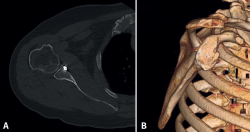

A 55-year-old woman with hypothyroidism as the only medical history of interest was admitted due to right anterior glenohumeral dislocation following a fall. The computed axial tomography (CAT) scan with three-dimensional (3D) reconstruction in en-face sagittal view of the glenoid cavity confirmed an acute glenoid fracture affecting 25% of the joint surface as measured with the "perfect circle" technique using the linear method to determine percentage bone loss(7,8). Measurement moreover found the displacement of the fragment to be 9.5 mm (Figure 1). Taking into account the size of the fragment and its displacement, arthroscopic surgery was decided for reduction and fixation using the button system.

Figure 1. Presurgical images of the lesion. A: computed tomography view (axial section) showing the displaced fracture of the anterior glenoid labrum; B: three-dimensional reconstruction confirming displacement and a fracture fragment size corresponding to 25% of the glenoid surface, using the perfect circle method with linear calculation; C: computed tomography view (sagittal section) of the glenoid cavity, confirming displacement of the fragment (9.5 mm).